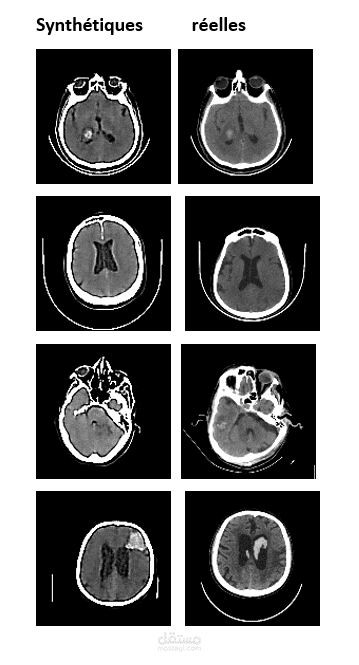

تطوير نموذج cVAE لتوليد صور أشعة مقطعية صناعية للسكتة الدماغية. الهدف هو موازنة البيانات وتحسين أداء نماذج التصنيف الطبية.